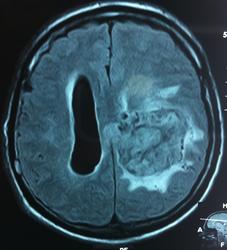

T1+C

Т2

FLAIR

Изначально по КТ я так предпологал, а теперь на 100% уверен, разве МРТ это не показало? Гистологически - менингиома, опухоль мозговой оболочки. Покажите, пожалуйста, образование где-нибудь прилежит к костям, где есть мозговая оболочка? Я не вижу, зато отчетливо вижу в левом боковом желудочке из оболочек сосудистого сплетения. Что вас еще смущает? По-моему, предостаточно фактов, чтобы развеять все сомнения.

Мне видится так. Иначе в данной локализации просто неоткуда расти оболочечной опухоли. На контрольной КТ, после декомпрессии, когда срединные структуры стали действительно срединны, правое обызвествленное сосудистое сплетение видно отчетливо, а левое, где оно? Ведь если бы образование компремировало, то после операции, когда часть мозга пролабировало в трепанационное отверстие мы бы увидели и левое сосудистое сплетение, но оно интимно связано с образованием и даже "потянулось" за ним в сторону декомпрессионного отверстия, потому что это и есть "росток" откуда выросла опухоль.

У меня вопрос (извините, если тупой - я-не волшебник, я только учусь=) - мне кажется, что в центре образования есть участки пустоты потока (сосуды), а разве менингиома склонна к такому неоангиогенезу? просто прочитала все вышенаписанное, вроде полностью согласна, но как вариант закралась мысль о сосудистой опухоли из сплетения бок.желудков. Если я совсем не права, прошу пояснить. Хочется все понимать уже на первых годах работы.) Заранее благодарю.